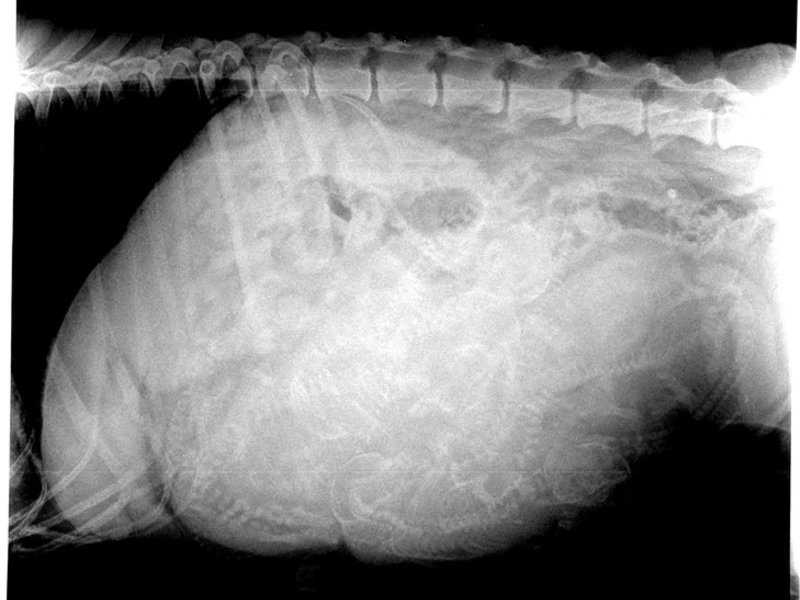

"Rose" oder mit vollem Namen "Killarney's Heartland Aim high Caribbean Sunset" ist der erstgeborene Welpe unseres A-Wurfes (Faizah Killarney tom Etthewide x Matakima Caito).

Rose hat sehr schnell selbst entschieden, dass sie diejenige ist, die bei uns bleiben wird.

Optisch ihrer Mutter sehr ähnlich hat sie allerdings eher das Temperament der Pharaohs und weiß doch sehr genau was sie will und was bitte nicht. Man munkelt sie hätte viel von ihrer Großmutter väterlicherseits, ich bin gespannt!

Rose hat ihren eigenen Kopf, hat vor nichts und niemandem Angst, springt allein auf die Couch, auf's Dach des Entehauses...kann viele Dinge allein und macht unser Leben deutlich bunter.

Sie ist ein wahr gewordener Traum und ich bin gespannt, wohin uns diese Reise mit dieser kleinen Dame führt.